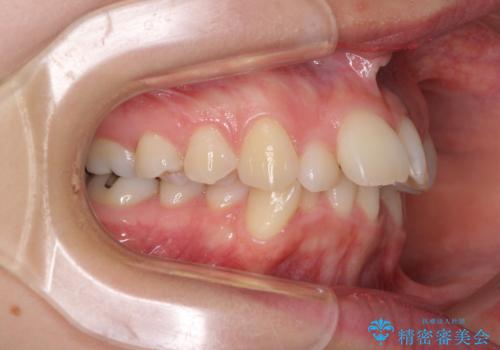

デコボコで飛び出した前歯 ワイヤー装置による抜歯矯正

- 上下前歯のデコボコと、飛び出した前歯を気にして来院された患者様です。

口元を積極的に引っ込めるために、上下左右の小臼歯計4本を抜歯することとしました。

咬み合わせが深く、咬合力強いため、補助装置を使用しながら積極的に口元を下げることとしました。